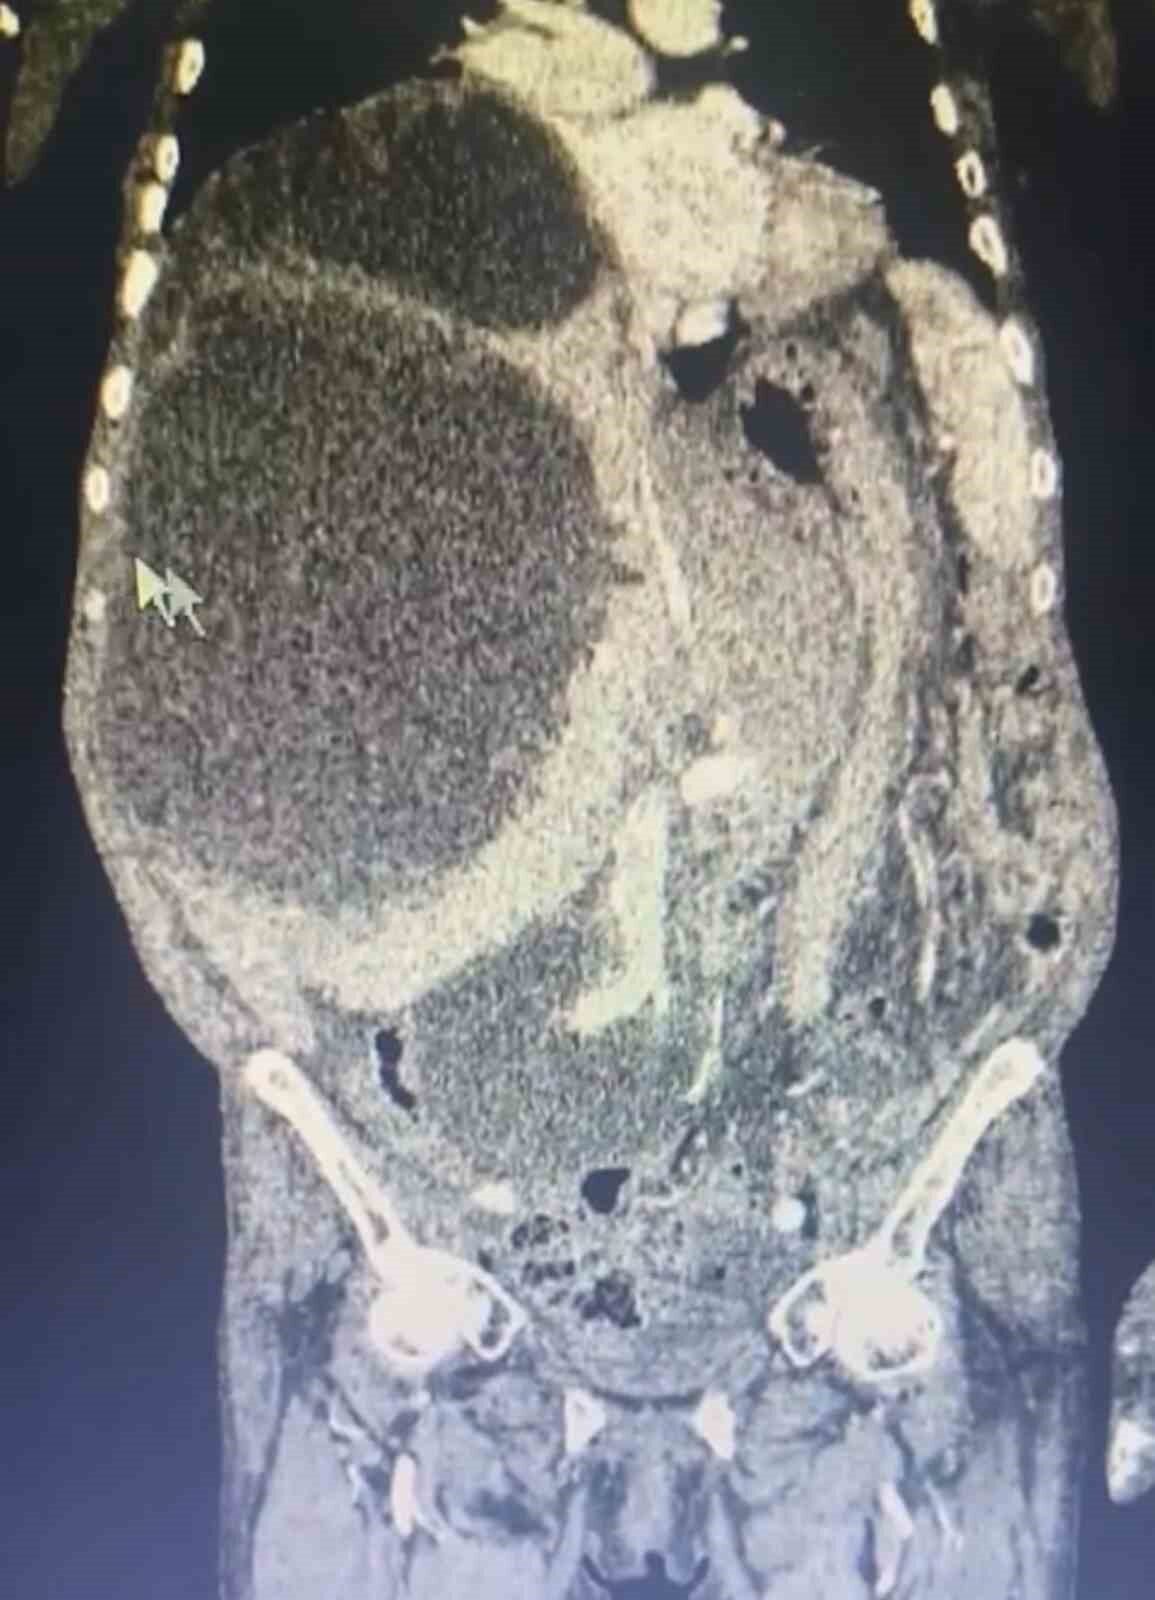

Kistlerin büyüklüğü dikkat çekerken Genel Cerrahi Uzmanı Opr. Dr. İsmet Çelik, dünya literatüründe tüm karnı dolduran ve 90 santime ulaşan kist görmediklerini belirterek Taşdelen’e yapılan gerekli tetkikler ve görüntüleme sonucu karaciğerinde üç adet kedi-köpek kisti (hidatik kist) tespit ettiklerini ifade etti. Çelik, başarılı geçen ameliyatın ardından hastanın sağlık durumunun iyi olduğunu ve sürecin yakından takip edildiğini belirtti.

Dünya literatüründe tüm karnı dolduran ve 90 santime ulaşan kist görmediklerini ifade eden Çelik, “Asiye Hanım, maalesef ihmal edilmiş bir hastamız. Bu kist, kedi ve köpeklerin dışkısı ve yediği yiyeceklerle bulaşan bir hastalık. Bu kist, genellikle tesadüfen yakalanabilir. Karaciğere yerleşir. Bu hastamızda da durum öyle olmuş. Ameliyat olamayacağı söylenip eve yollanmış. Bizler detaylandırıp ameliyat kararı aldık. Hastamızın karaciğerinde 3 ayrı kist vardı. Tüm karnı kist ile kaplıydı. 2 tanesinin tamamına çıkardık. Diğerini ise kontrolle alarak içini boşalttık. Dünya literatüründe tüm karnı dolduran ve 90 santime ulaşan kist görmedik. Ameliyatımız 2 saat sürdü. Hastamızın safra yolları kontrol edildi. Hastamızın durumu gayet iyi. Solunum cihazından bağımsız olarak kendi başına solunum yapabiliyor. En korktuğumuz şey; alerjik bir durumun olması. 90 santim çapındaki kist vücuda yayıldığı zaman alerjik bir durumda hastanın ölümüne sebep olabilmesi. Göremediğimiz yayılımlar için tedbir alıyoruz” diye konuştu.

YAPILAN TETKİKLERİNDE HASTANIN KARACİĞERİNDE ÜÇ ADET KİST TESPİT EDİLDİ.